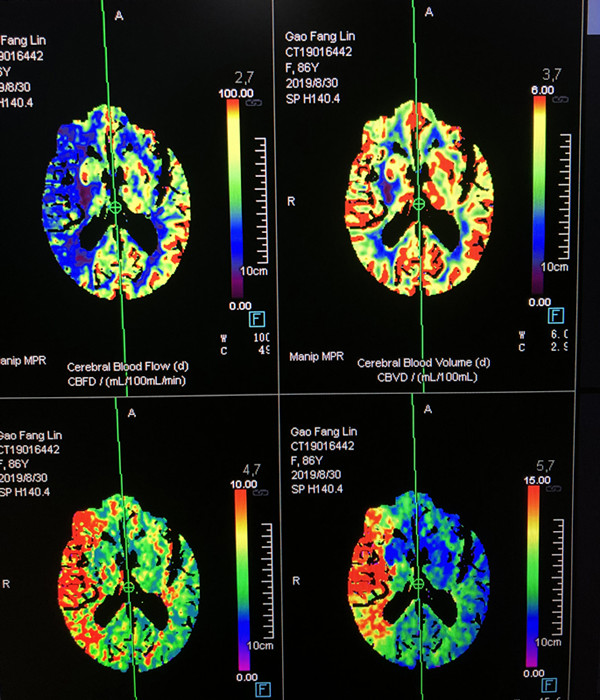

术前CTP提示右侧颈内动脉分布区血流减少